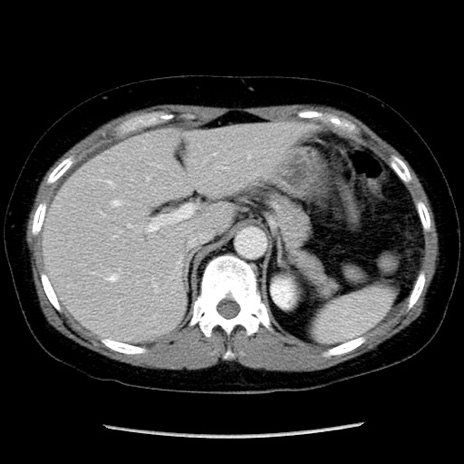

冠状断像